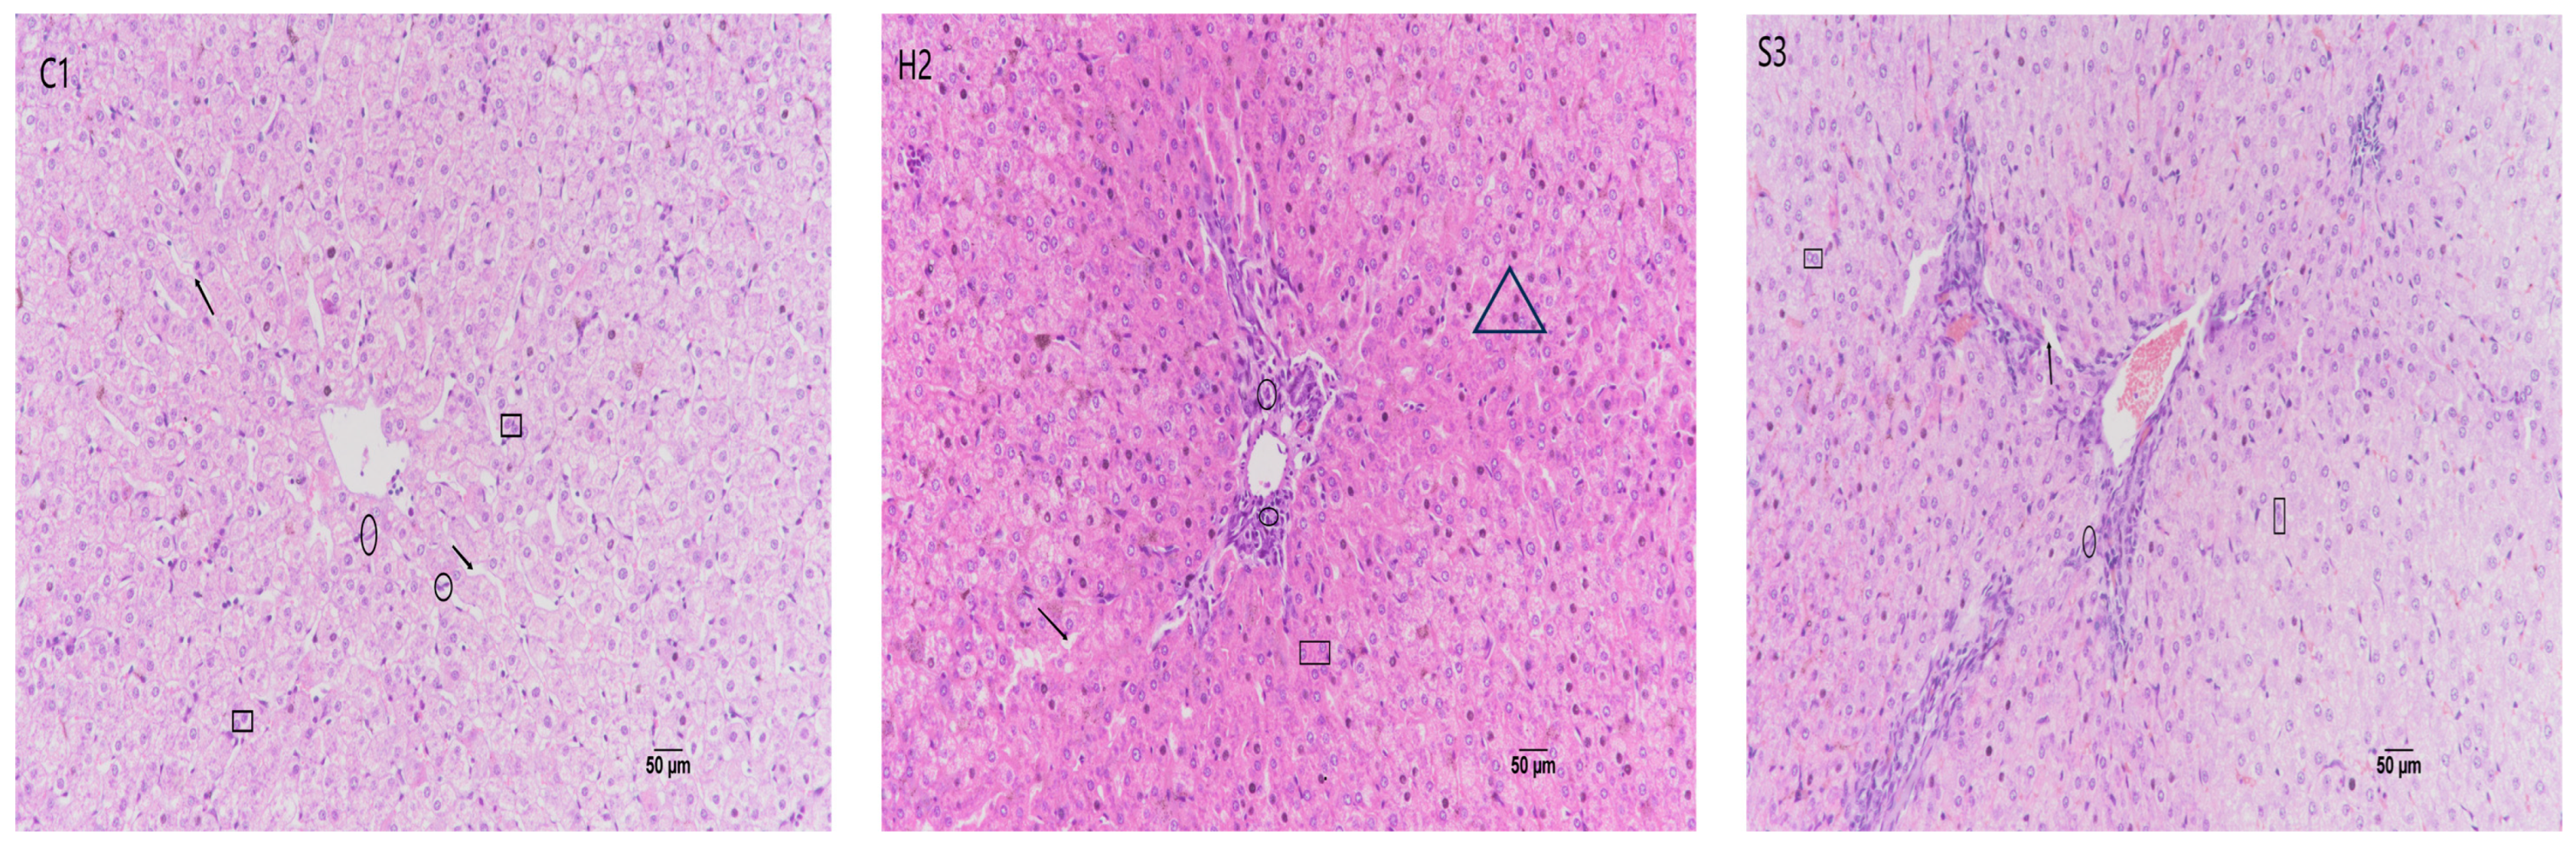

3.5. Effect of SA Addition to High-Concentrate Diets on Sheep Liver Tissue Sections